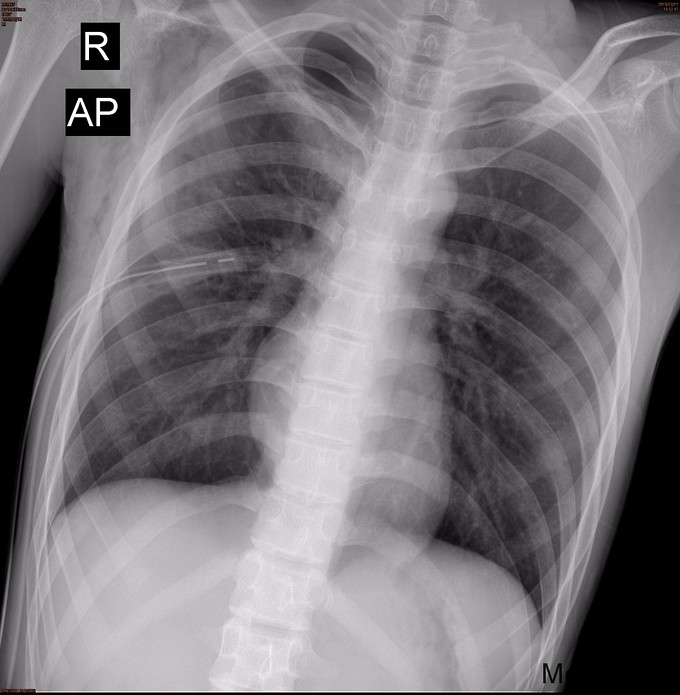

15岁男性患者,因突发右侧胸闷胸痛伴咳嗽2周收住入院,呈阵发性干咳,无气促、心悸、心慌、恶心、呕吐、乏力、视物模糊、咳痰、咯血、痰中带血等表现,到当地医院就诊,行胸片提示右侧自发性气胸,予以行胸腔穿刺抽气治疗2次,效果欠佳,予以行胸腔闭式引流术,仍有持续漏气,为求进一步治疗来我院就诊。有过敏性哮喘病史5年。

查体:患者呈瘦高类型,胸廓无畸形,肋间隙变窄,左肺叩诊呈清音,呼吸音清,右肺叩诊过清音,呼吸音弱,双肺未闻及异常呼吸音及干、湿罗音。辅查: 胸部CT1.右侧气胸,右肺组织受压缩约80-90%;右侧胸腔内见一引流管留置; 2.双上肺肺大疱; 3.右侧腋下、胸壁皮下气肿。